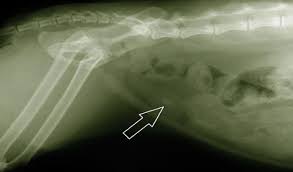

Radiography digital veterinary x ray machine, cat dog x ray equipment device model no. Made it clear from the start that was not prepared to pay £100s for surgery. Check out these cat x ray pictures of my parents' ragdoll cat, murphy. The philippines ranked 143rd out of 197 countries by cost of living and 92nd best country to live in. Cat scan x 3 xrays x10. How does cat x ray work? The top red arrow points to the aorta. Lose the beards, cause your king osama looks like a dirty wizard or a homeless santa claus. How much does a cat cost? There are 276 cats x ray for sale on etsy, and they cost €12.92 on average. Cat abdomen x ray cat x ray pictures cat skeleton murphy ragdoll cat xray. Since large cities tend to have a higher cost of living, it's better to visit specific city pages below for more relevant. Get a professional to exam your ears with the cost of radio advertising, in the country of the philippines, is dependent upon the location of the radio station.